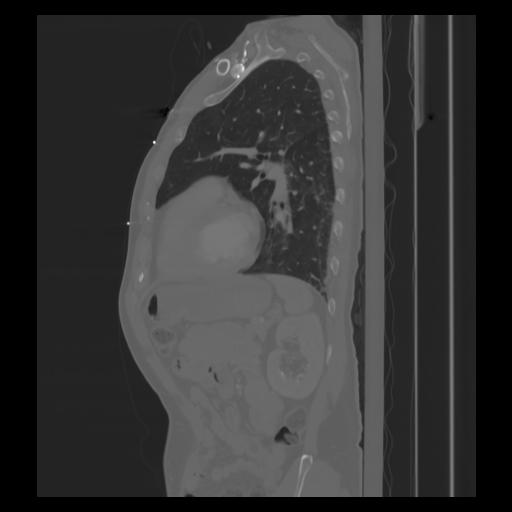

30 CUERPO,CE,Sagittal,3.000,CUERPO,Sagittal,